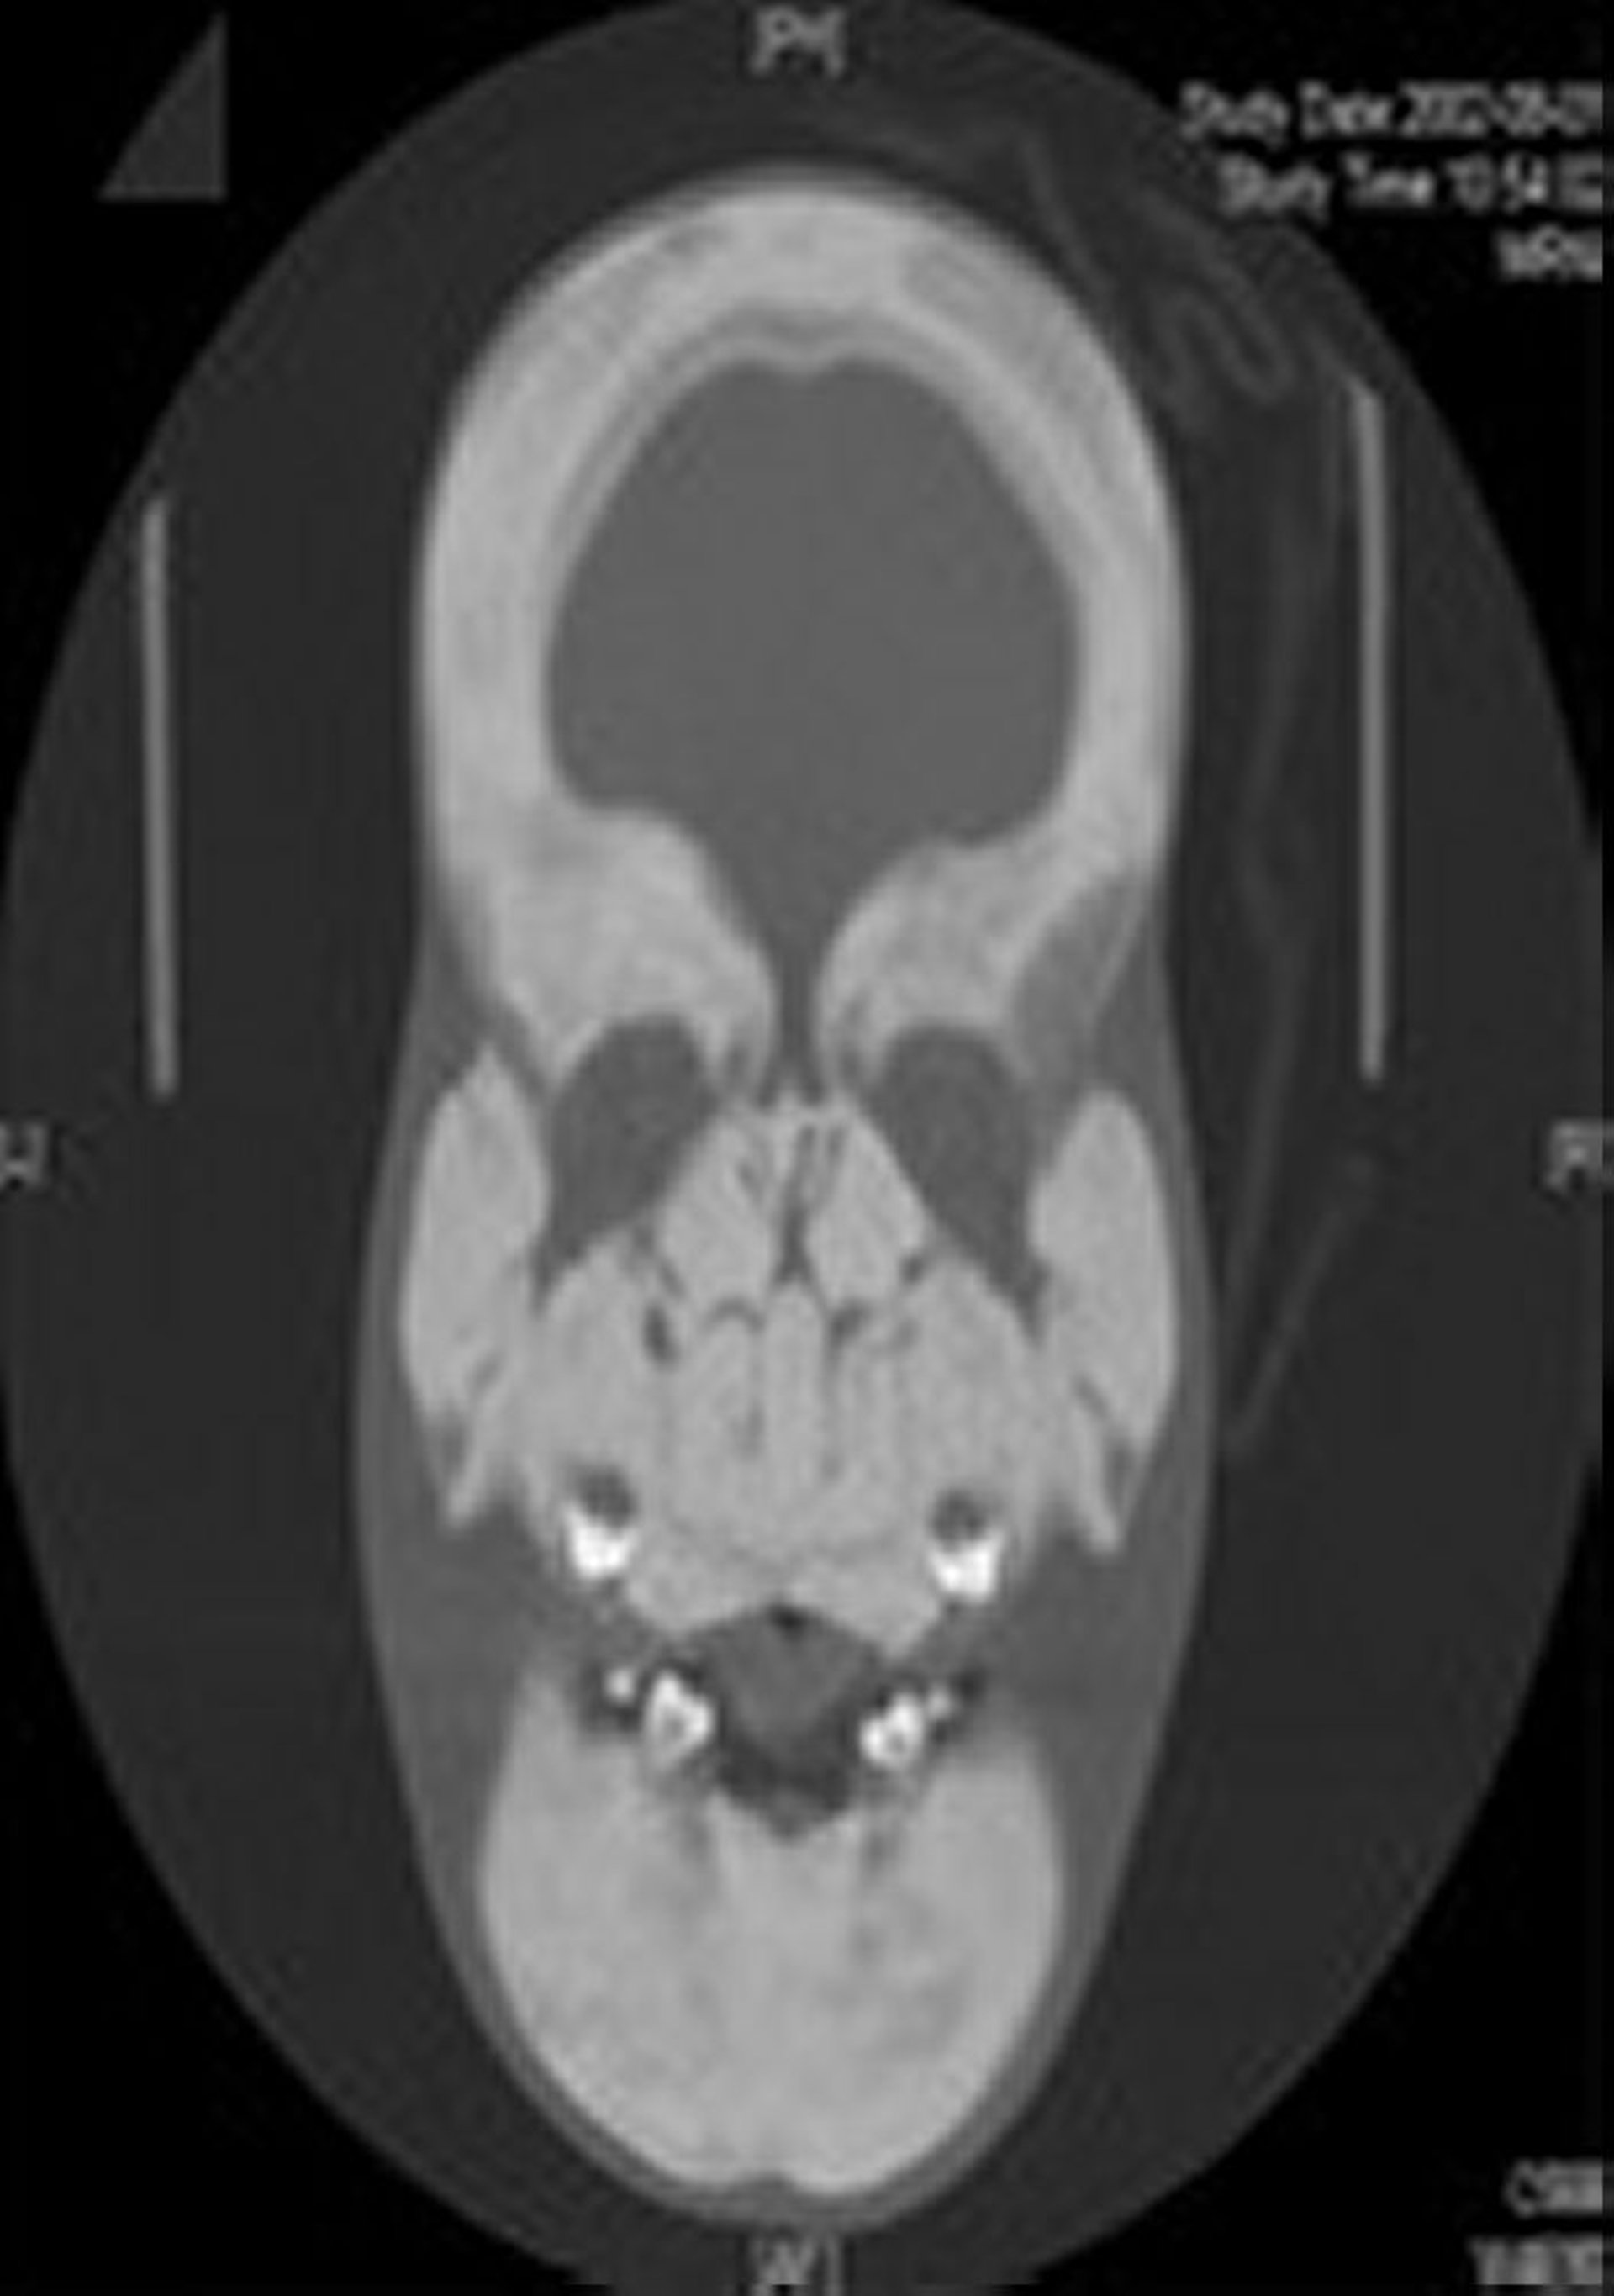

Esclerosteose (radiografia)

Essa imagem mostra espessamento e esclerose acentuados do crânio e ossos faciais inteiros.